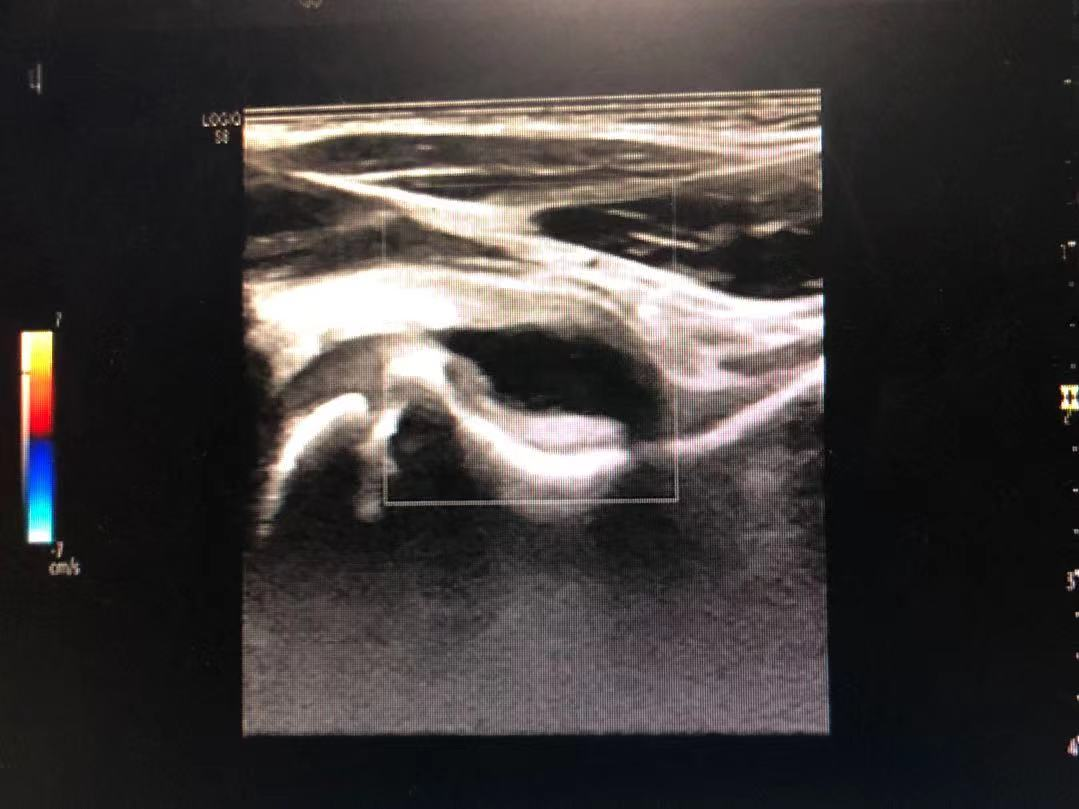

近日,长沙市中医医院(长沙市第八医院)骨伤科门诊接连接诊了几个3、4岁的小朋友,患儿家长说前一天还活蹦乱跳的,睡一觉起来就说腿好痛,走路一瘸一拐,有的甚至不能下床走路。医生予其系统检查后,排除结核、感染、髋关节发育不良等疾病,髋关节彩超检查发现患儿疼痛侧髋关节前隐窝隆起,前隐窝内出现了大于2mm的积液暗区,部分患儿还合并了滑膜增生,诊断为髋关节滑膜炎。

此病的临床诊断既往主要依靠临床表现及骨盆平片检查,随着高频超声的发展,对小儿髋关节周围软组织及关节腔的显示越来越来清晰,髋关节的超声检查方便快捷且无辐射损伤,可明确诊断,为此病的首选检查方式。